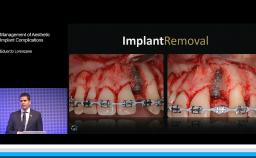

Dean Morton discusses how to plan for success rather than failure and how to effectively manage problems when they occur.

The etiology of tooth loss and the goals of therapy provided by the implant clinician are also covered. The lecture includes excellent use of clinical cases to highlight common complications in implant dentistry to include biological, mechanical, and technical complications and how to avoid them.